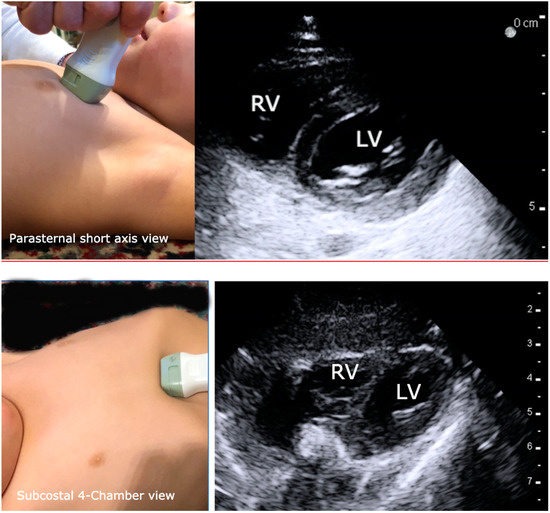

The subcostal 4-chamber (S4CH) view and the parasternal short axis (PSAX) are easiest to learn and ideal for assessing left ventricle (LV) size and systolic function, movement of the intraventricular septum, and to evaluate for pericardial effusion or emboli (Figure 4). The parasternal short axis PSAX window is generally the most accessible in children who are draped for surgery (Figure 4). The parasternal long-axis (PLAX) view is best for gross valvular assessment. The S4CH view is the recommended imaging window during cardiopulmonary resuscitation CPR [49,50,51] because it is the least disruptive of chest compressions. When possible, several views should be obtained to confirm the interpretation.

Figure 4.

Images that illustrate proper transducer placement and resultant normal images for the parasternal short axis and subcostal 4-chamber views of the heart. RV = right ventricle and LV = left ventricle.